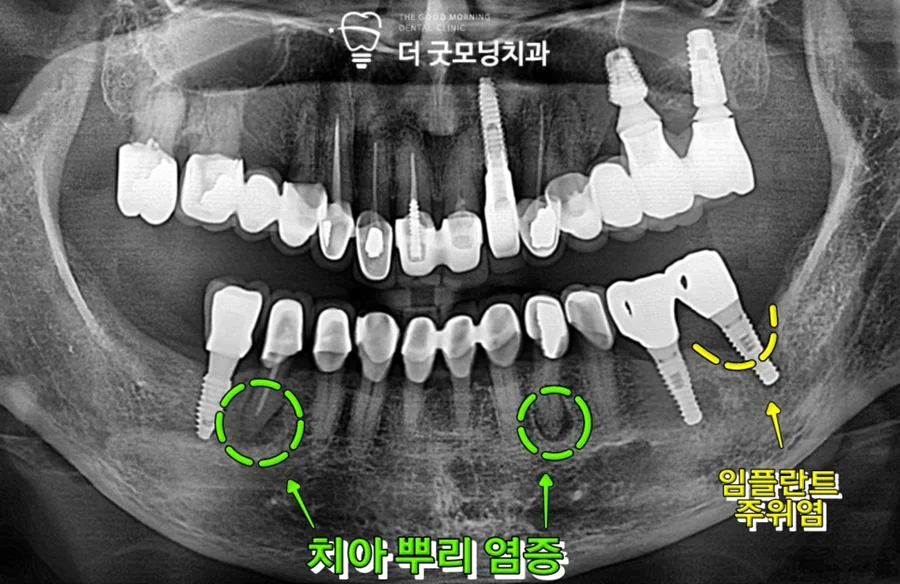

또한 양측 하악 2곳의 자연치 치근단에도 염증이 이환되어 있어 추가 치료 계획도 함께 수립하였습니다.

•     37번 임플란트: 주위염으로 진행된 픽스처 제거 후 당일 즉시 재식립 + 뼈이식

•     오른쪽 하악 어금니: 기존 신경치료 후 병소 이환 → 발치 후 임플란트 식립

•     왼쪽 송곳니: 보철 내부 충치 진행 → 발치 후 임플란트 식립